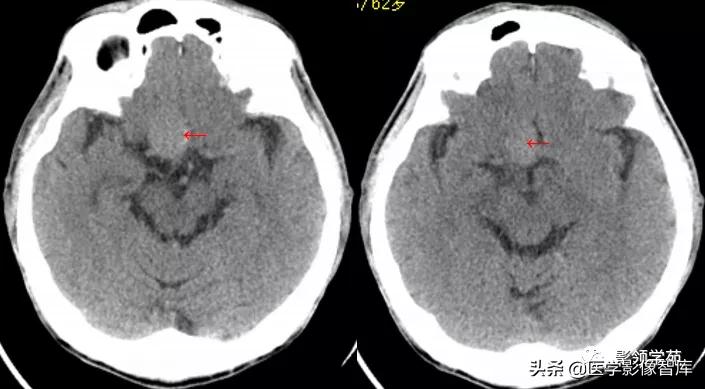

女 58岁,头晕、呕吐,桥脑右前方见一类圆形

高低混合(有血栓)T1及T2信号影,边界清楚、锐利。

明显不均匀强化(瘤内有血栓)。与基底动脉分界不清

头颅CTA:基底动脉起始部血管局部瘤样突起(宽基底),无占位效应。